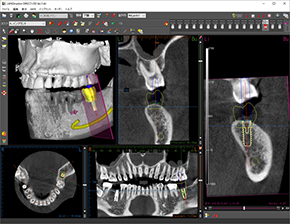

3D画像による精密なシミュレーション

当院では、京セラ社のインプラントシミュレーションシステムを導入しています。

インプラント治療を行う前に、専用のシミュレーションソフトを使用し、CTデータからインプラントのオペ計画を立案しています。

そして、患者様ごとにサージカルガイドと呼ばれるインプラントの埋入位置や角度を指定する装置を作成し、使用しています。3D解析による精密な診査・診断を行うことで、より安全・安心に、高度で優れたインプラント治療をご提供することができます。